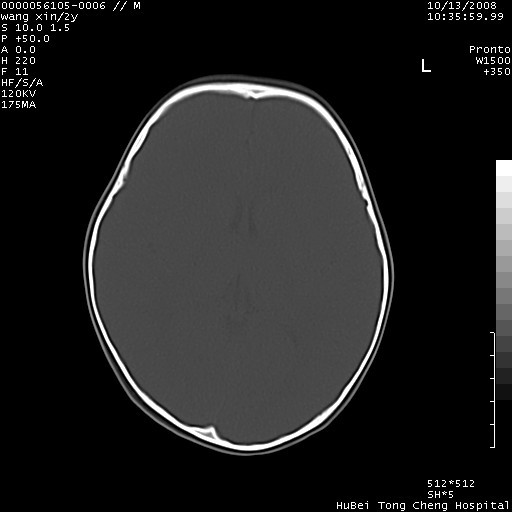

标题: PED1611:F,2Y。右侧额部小包块,光整,质硬,边界清楚,无 [打印本页]

标题: PED1611:F,2Y。右侧额部小包块,光整,质硬,边界清楚,无

病灶临近颅缝,支持考虑表皮样囊肿可能,病灶区要薄扫就好了

右额骨内板压迫性变薄,呈椭圆形膨胀性骨吸收和低密度区,其间可见小斑片状致密影,-支持表皮样囊肿